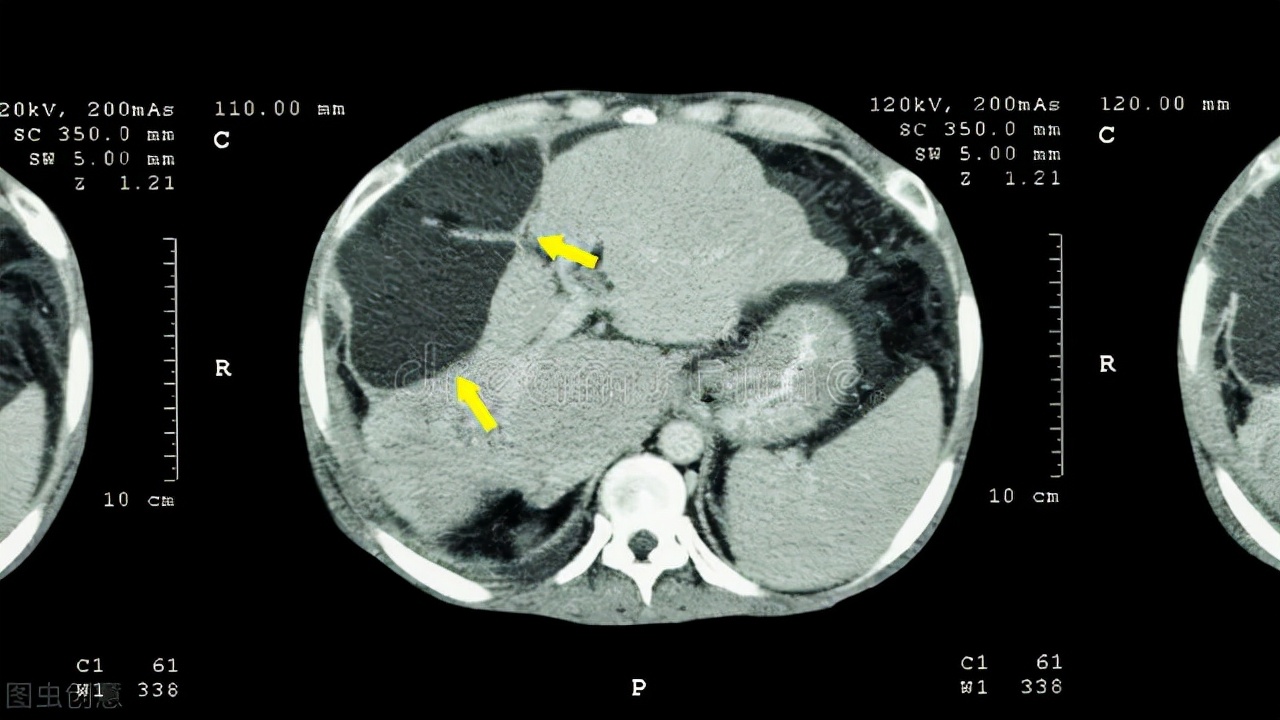

无奈之下,李叔叔就去了医院就诊,接诊医生仔细询问了情况后,就给他开了腹部CT的检查。 检查结果出来后,发现肝脏有一个肿块,而且还发生了转移,初步诊断为肝癌。 接诊医生把情况告诉了李叔叔,并且建议他住院接受正规治疗。李叔叔听了接诊医生的言论后,内心特别的排斥,所以就说出了文章开头的那句话。